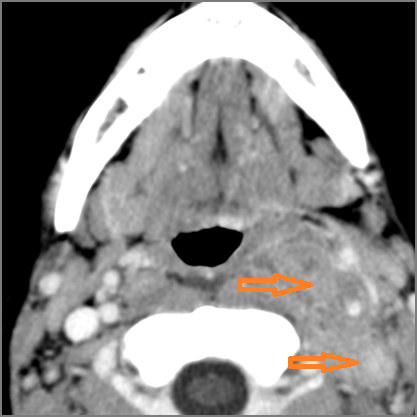

There is excessive enhancement or thickening of the mucosa within in the hypopharynx, larynx or trachea. [Yes/No]

There is edema within in the hypopharynx, larynx or trachea. [Yes/No]

There is abscess within in the hypopharynx, larynx or trachea. [Yes/No]

There is edema within the adjacent deep neck, retropharyngeal and/or prevertebral spaces [Yes/No]

There is abscess within the adjacent deep neck, retropharyngeal and/or prevertebral spaces. [Yes/No]